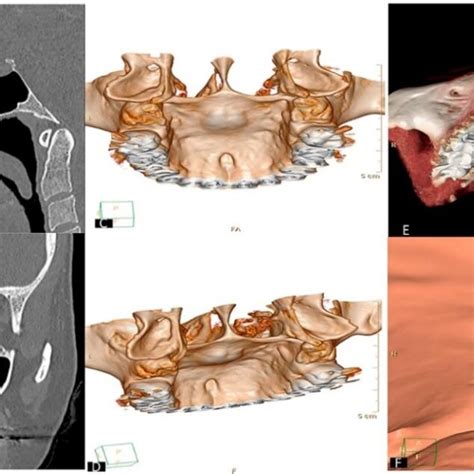

Si notas un bulto duro en el centro del paladar, es muy posible que se trate de un torus palatino. El torus es básicamente un crecimiento excesivo de hueso en el paladar duro. Suele aparecer en la línea media del paladar y tiene una consistencia ósea (firme al tacto). No duele ni crece rápidamente, más bien se desarrolla lentamente a lo largo de los años.

Mucha gente convive con un torus palatino sin darse cuenta, ya que suele ser asintomático y benigno. De hecho, se considera una variante anatómica normal en un porcentaje de la población.

En la mayoría de los casos no hace falta tratar un torus palatino. Solo recomendaríamos su extirpación quirúrgica si crece tanto que interfiere con la masticación, la pronunciación o la colocación de una prótesis dental, o si al paciente le molesta para su higiene.

Torus Palatino: Crecimiento óseo benigno en el paladar